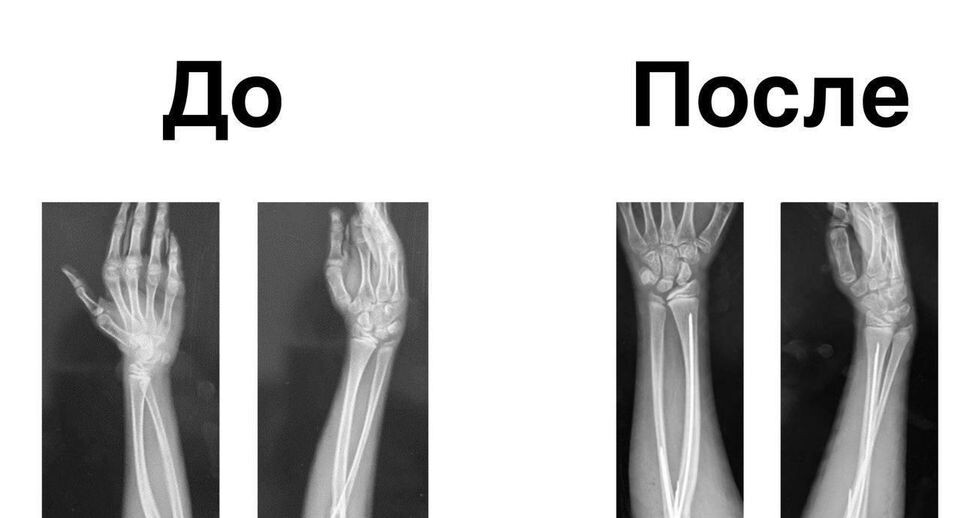

В ходе обследования у девочки выявили редкое заболевание опорно-двигательного аппарата — врожденный радиоульнарный синостоз. При нем наблюдается сращение локтевой и лучевой костей.

Как рассказал заведующий отделением травматологии и ортопедии № 2 Алексей Иванов, пациентке провели операцию, в ходе которой руке придали анатомически правильное положение.

«Мы провели операцию, в ходе которой выполнили пересечение сросшихся костей на уровне сращения и повернули их в анатомически правильное положение. Это значительно улучшит самообслуживание и обеспечит функциональность руки. После операции мы зафиксировали кисть специальными спицами», — сказал он.